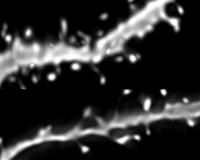

Adult mice without any ApoE or with the human ApoE4 gene produced new neurons, but the neurons did not mature normally. These neurons had short and sparse branches compared with neurons produced by mice with the human ApoE3 gene. The ApoE4 neurons also had fewer spines, where connections are made with other neurons.

This suggests that human ApoE3 is better than ApoE4 at helping new neurons grow, branch out, and form connections with other neurons.